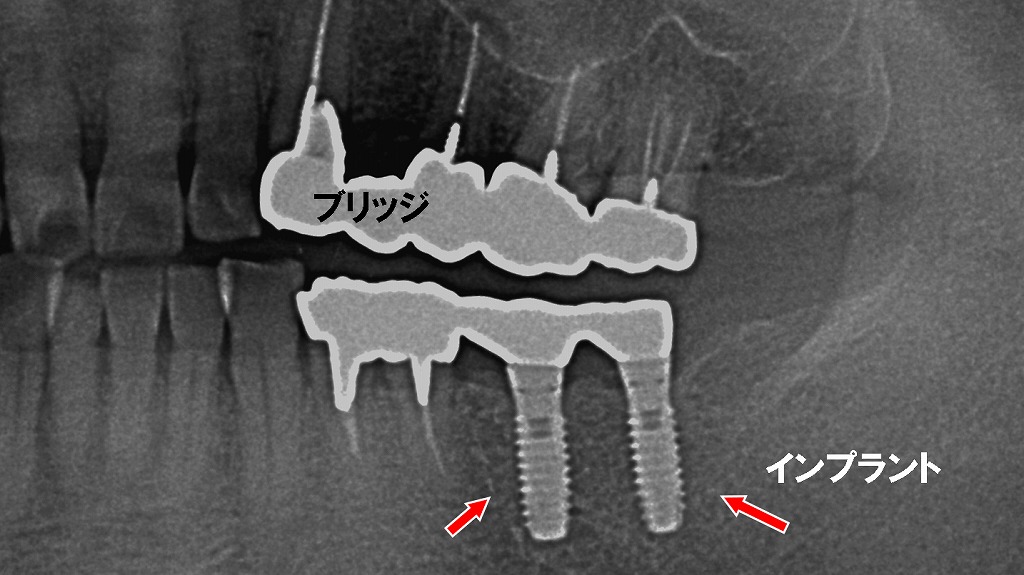

- 上顎の第一大臼歯・第二小臼歯・第一小臼歯の3本が下方向に挺出

- 噛み合う歯がないため、下の歯茎に向かって伸びている

欠損した歯を放置すると、噛み合う相手の歯が支えを失い、徐々に挺出(歯が伸びる現象)を起こします。挺出が進むと噛み合わせが乱れ、歯周病の悪化や破折リスクが高まることがあります。

画像では、失った歯の部位にインプラント治療を行い、上部にはブリッジ補綴を装着することで噛み合わせを適正に回復しています。歯を失った際は、放置せず早期に治療を行うことで、周囲の歯への悪影響を防ぐことができます。